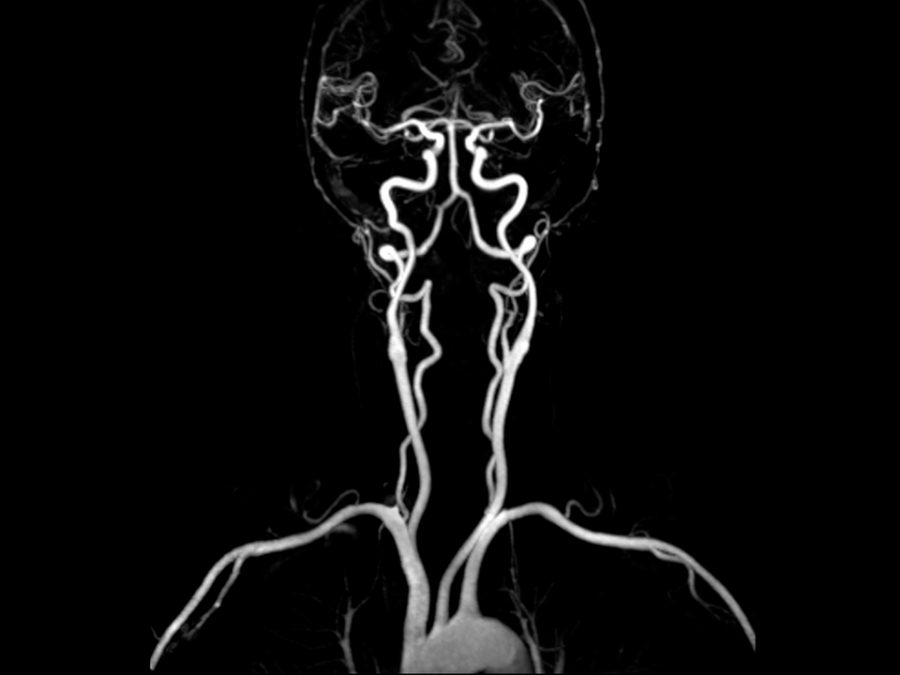

La sua elevata definizione consente inoltre un appropriato studio delle sezioni destre del cuore spesso di difficile valutazione con altre metodiche, ecocardiografia compresa. Qualora la tecnica venga applicata al distretto vascolare, generalmente per la definizione di anomalie di decorso o diametro di arterie, si parla di ANGIORM specificandone il distretto (ad es cerebrale, toracico, addominale…).